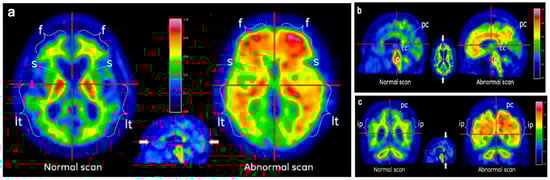

- Mountz, J.M.; Laymon, C.M.; Cohen, A.D.; Zhang, Z.; Price, J.C.; Boudhar, S.; McDade, E.; Aizenstein, H.J.; Klunk, W.E.; Mathis, C.A. Comparison of qualitative and quantitative imaging characteristics of [11C]PiB and [18F]flutemetamol in normal control and Alzheimer’s subjects. NeuroImage Clin. 2015, 9, 592–598. [Google Scholar] [CrossRef] [PubMed]

- Buckley, C.J.; Sherwin, P.F.; Smith, A.P.L.; Wolber, J.; Weick, S.M.; Brooks, D.J. Validation of an electronic image reader training programme for interpretation of [18F]flutemetamol β-amyloid PET brain images. Nucl. Med. Commun. 2017, 38, 234–241. [Google Scholar] [CrossRef] [PubMed]